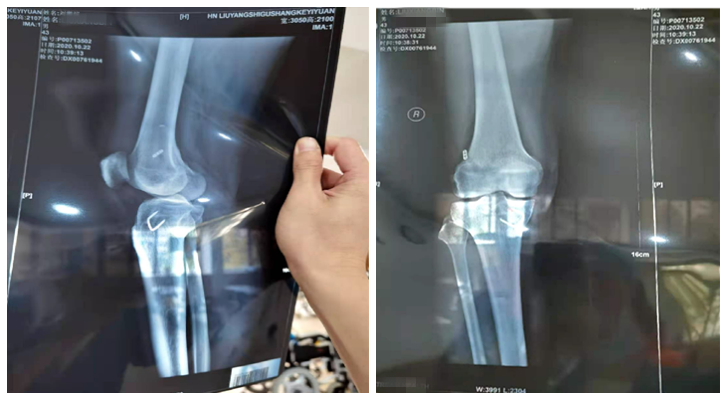

出院时,刘先生的情况

一个月后,刘先生康复出院了!出院时,他的右膝的肿胀已经消退,右膝关节活动正常,可重新返回学校任教!